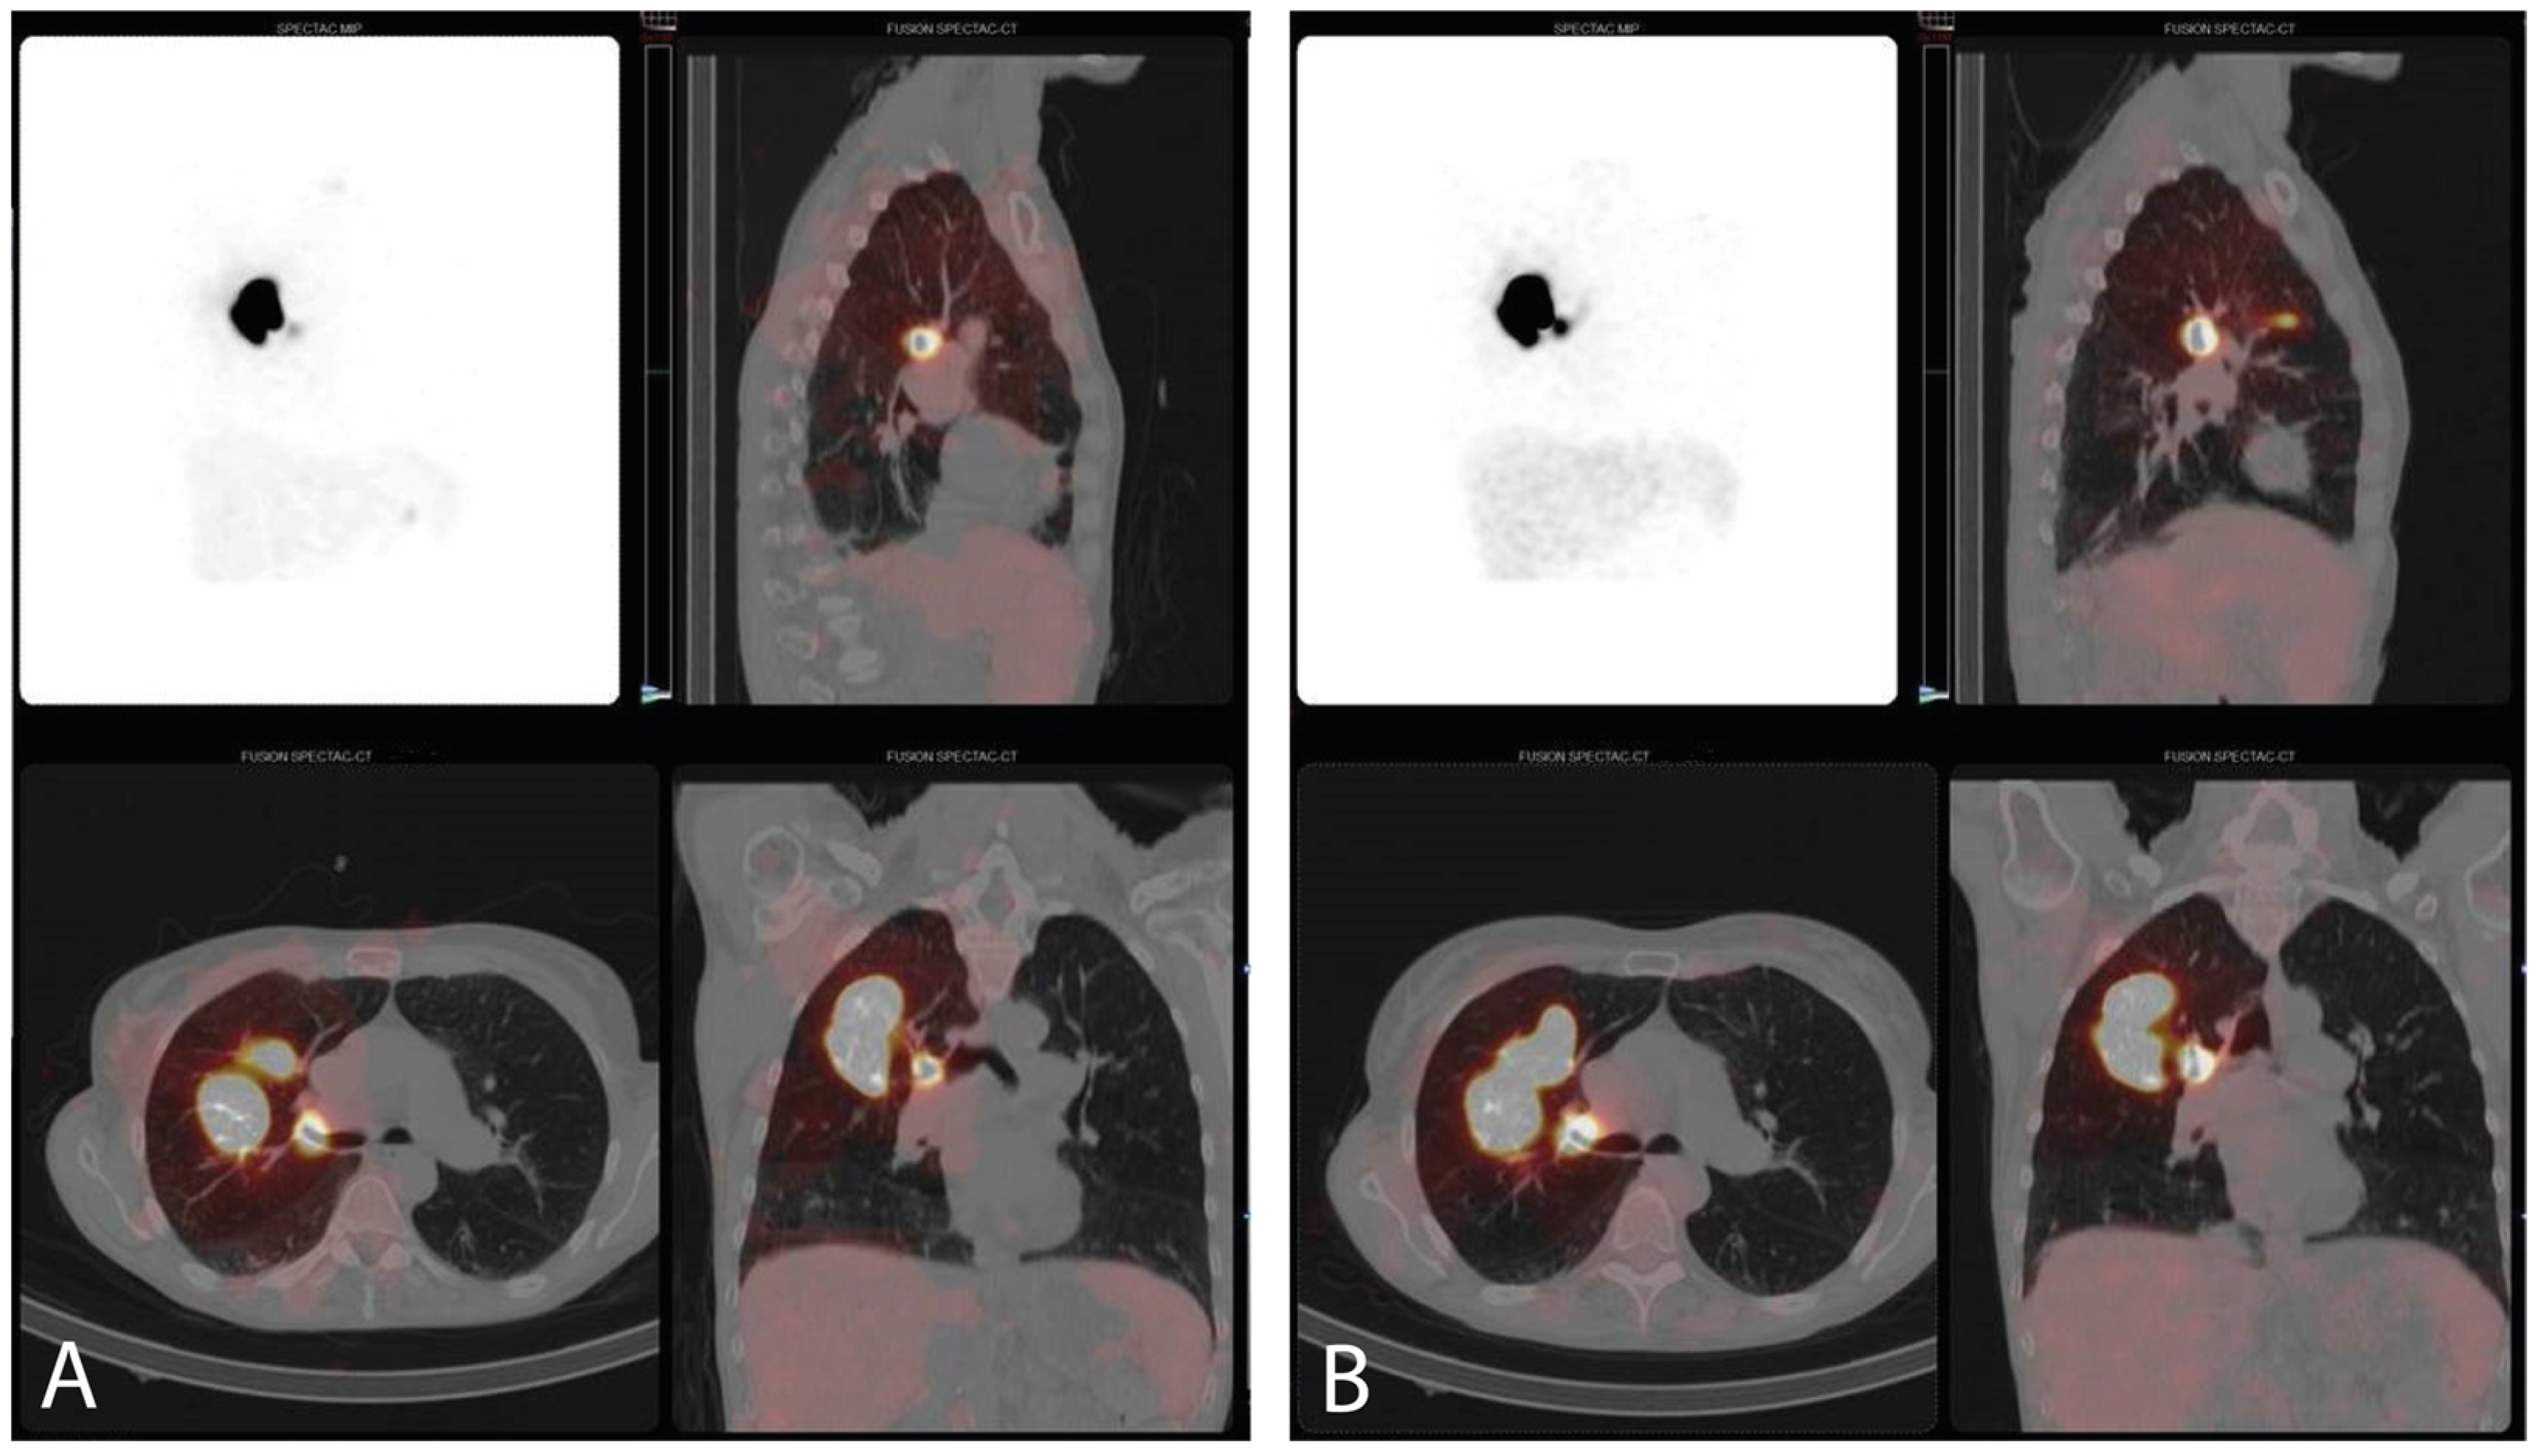

3.3. SPECT/CT Imaging and SLN Identification

| SPECT/CT imaging | Patients with an early scan, n (%) | 10 (32.3%) | |

| 02:28 (±01:02) | ||

| Patients with a late scan time, n (%) | 30 (96.8%) | ||

| 04:19 (±00:55) | ||

| SLN identification, all scan times, n (%) | 10 (32.3%) | ||

| 5 (50.0%) | ||

| 9 (30.0%) | ||